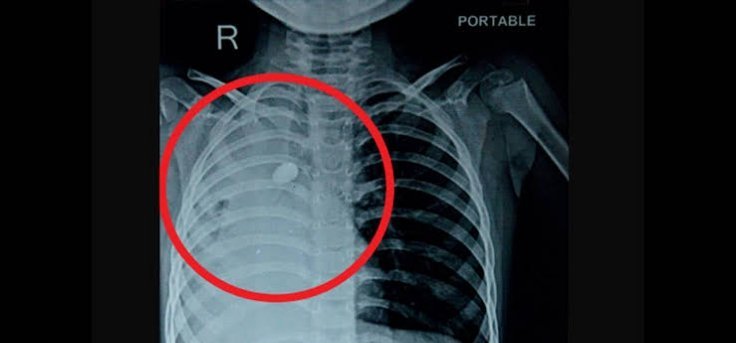

ऋषिकेश : सांस की नली में रोढ़ी बजरी की गिट्टी फंसने से एक 7 वर्षीय बच्चे की जान पर बन आई। मासूम का जीवन बचाने के लिए माता-पिता उसे लेकर कई अस्पतालों में गए, मगर मामला गंभीर देख सभी ने हाथ खड़े कर दिए। ऐसे में जोखिम उठाते हुए एम्स के चिकित्सकों ने इलाज की उच्च तकनीक का उपयोग किया और सांस की नली से होते हुए फेफड़े में फंसी गिट्टी को बाहर निकालने में कामयाबी हासिल की। बताया गया कि यह गिट्टी खेल-खेल में बच्चे के गले से नीचे उतरकर सांस की नली में फंस गई थी।

इस बाबत जानकारी देते हुए पल्मोनरी मेडिसिन विभाग के एडिशनल प्रोफेसर डॉ. मयंक मिश्रा ने बताया कि टीम वर्क से संपन्न की गई इस प्रक्रिया से चिकित्सकों की टीम, बच्चे की श्वास नली में फंसी गिट्टी को बाहर निकालने में सफल रही। डॉ. मयंक ने बताया कि निकाली गई गिट्टी का साईज 1.5×1 सेमी. था। 16 जुलाई को ब्रोंकोस्कॉपी की प्रक्रिया संपन्न करने के बाद स्वस्थ होने पर बच्चे को पिछले सप्ताह एम्स से डिस्चार्ज कर दिया गया।